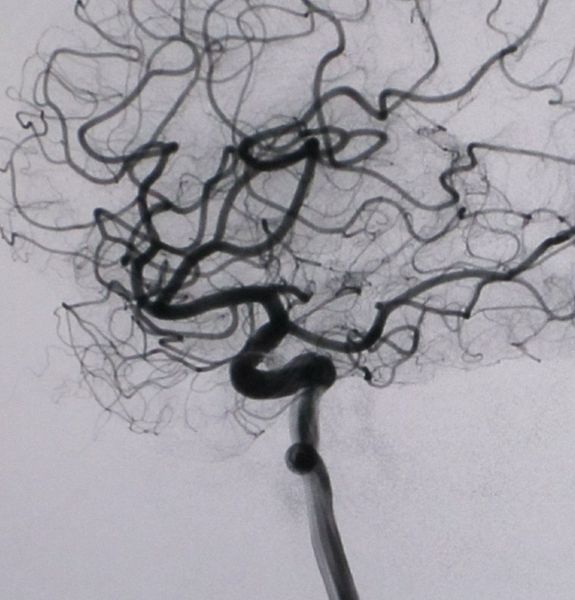

超选择性血管造影主要用于颅内肿瘤、脓肿、血肿、动脉瘤、动静脉畸形、动脉阻塞性病变以及颅脑外伤后等的诊断和定位。近年来由于采用了数字减影血管造影(DSA)技术,血管造影已经成为临床的一种重要的诊断方法,尤其在介入治疗中起着不可替代的作用。血管造影在头颈部及中枢神经系统疾病、心脏大血管疾病、及肿瘤和外周血管疾病的诊断和治疗中都发挥着重要作用。

通过DSA处理的图像,使血管的影像更为清晰,在进行介入手术时更为安全。

(1) 颅内及颈部血管性疾病。如动脉粥样硬化、栓塞、狭窄、闭塞性疾病、动脉病、动静脉畸形、主动脉瘤的形态、动静脉瘘等,其诊断灵敏度、特异性和正确性都很高达95—100%。颅内占位性病变,如颅内肿瘤、脓肿、囊肿、血肿等及颅脑外伤所致各种脑外血肿。